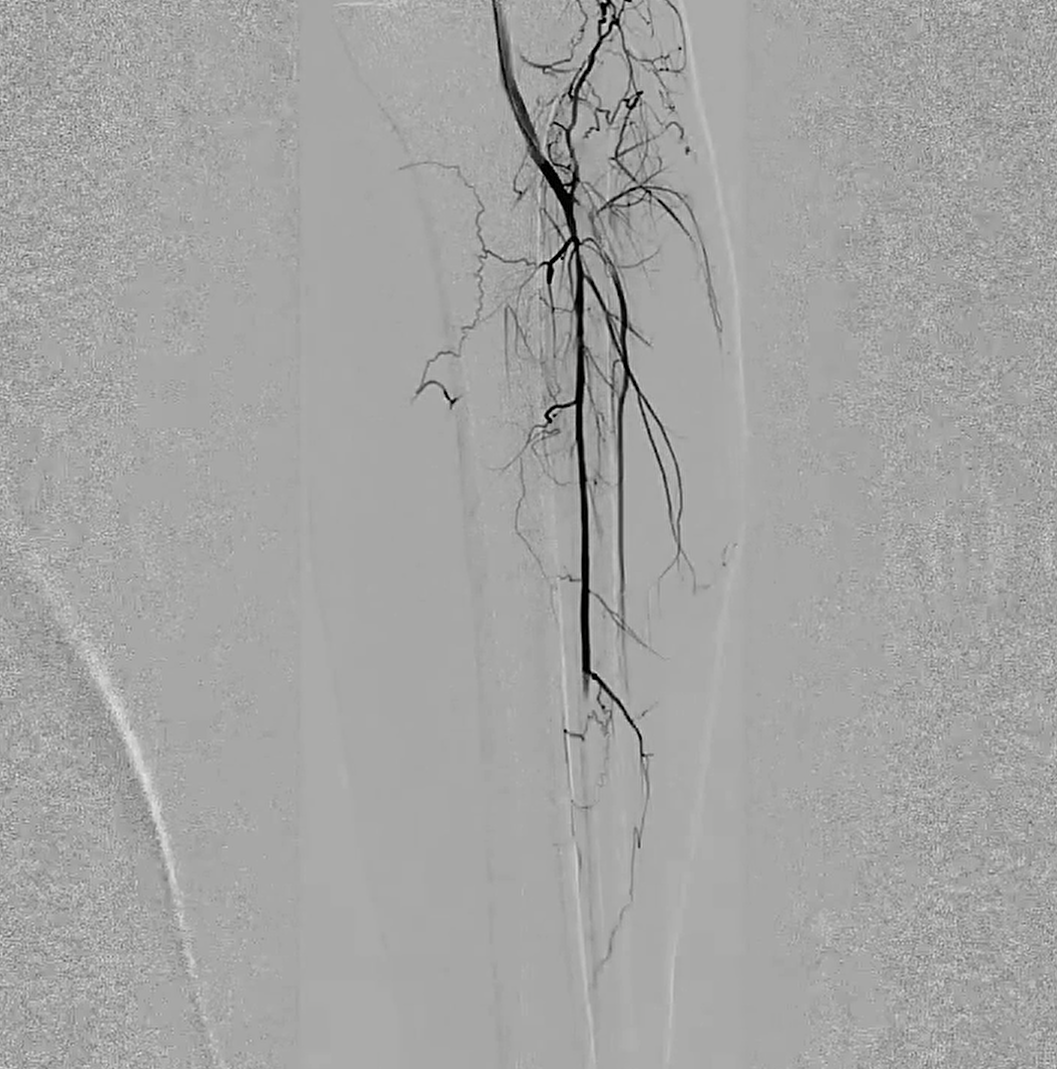

术后第2天患者左下肢皮温改善、花斑消失、可下地行走。

18个月彩超提示左股浅动脉至腘动脉覆膜支架通畅,腓动脉通畅。